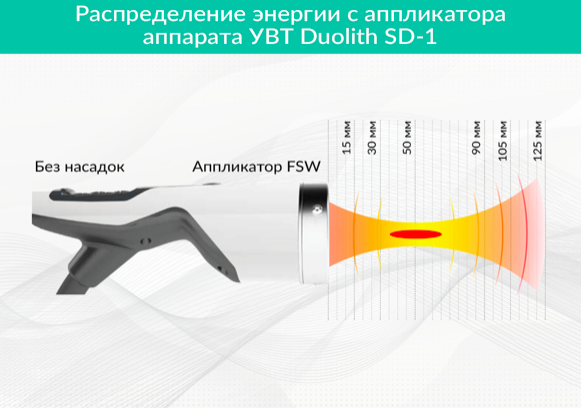

Часто можно увидеть так называемые диаграммы распределения энергии, где разными цветами отмечены зоны с разной плотностью потока энергии. Например, на рисунке 3 предоставлен пример диаграммы распределения энергии для аппарата УВТ Duolith SD-1, где красным условно обозначена ее максимальная плотность в районе фокусного пятна, желтым – минимальная плотность за пределами фокусного пятна.

Рисунок 3. Пример диаграммы распределения энергии для аппарата УВТ Duolith SD-1

Фокусированная ударная волна названа так, потому что фронты ее фокусируются в определенной области - фокусном пятне, имеющем высокую плотность энергии на единицу площади внутри пятна и относительно низкую плотность энергии областей вне его (Рисунок 1).

Фокусное пятно формируется с помощью специальных систем фокусировки аппаратов УВТ и имеет у наиболее распространенных аппаратов фокусное расстояние от нескольких миллиметров до 6 см. Фокусное расстояние – это расстояние от излучателя (аппликатора), прикладываемого к телу и используемого для проведения ударной волны внутрь тканей, до центра фокусного пятна. Фокусное расстояние может меняться с помощью насадок на аппликатор разной толщины, служащих своеобразными прокладками между излучателем и телом человека (Рисунок 2).